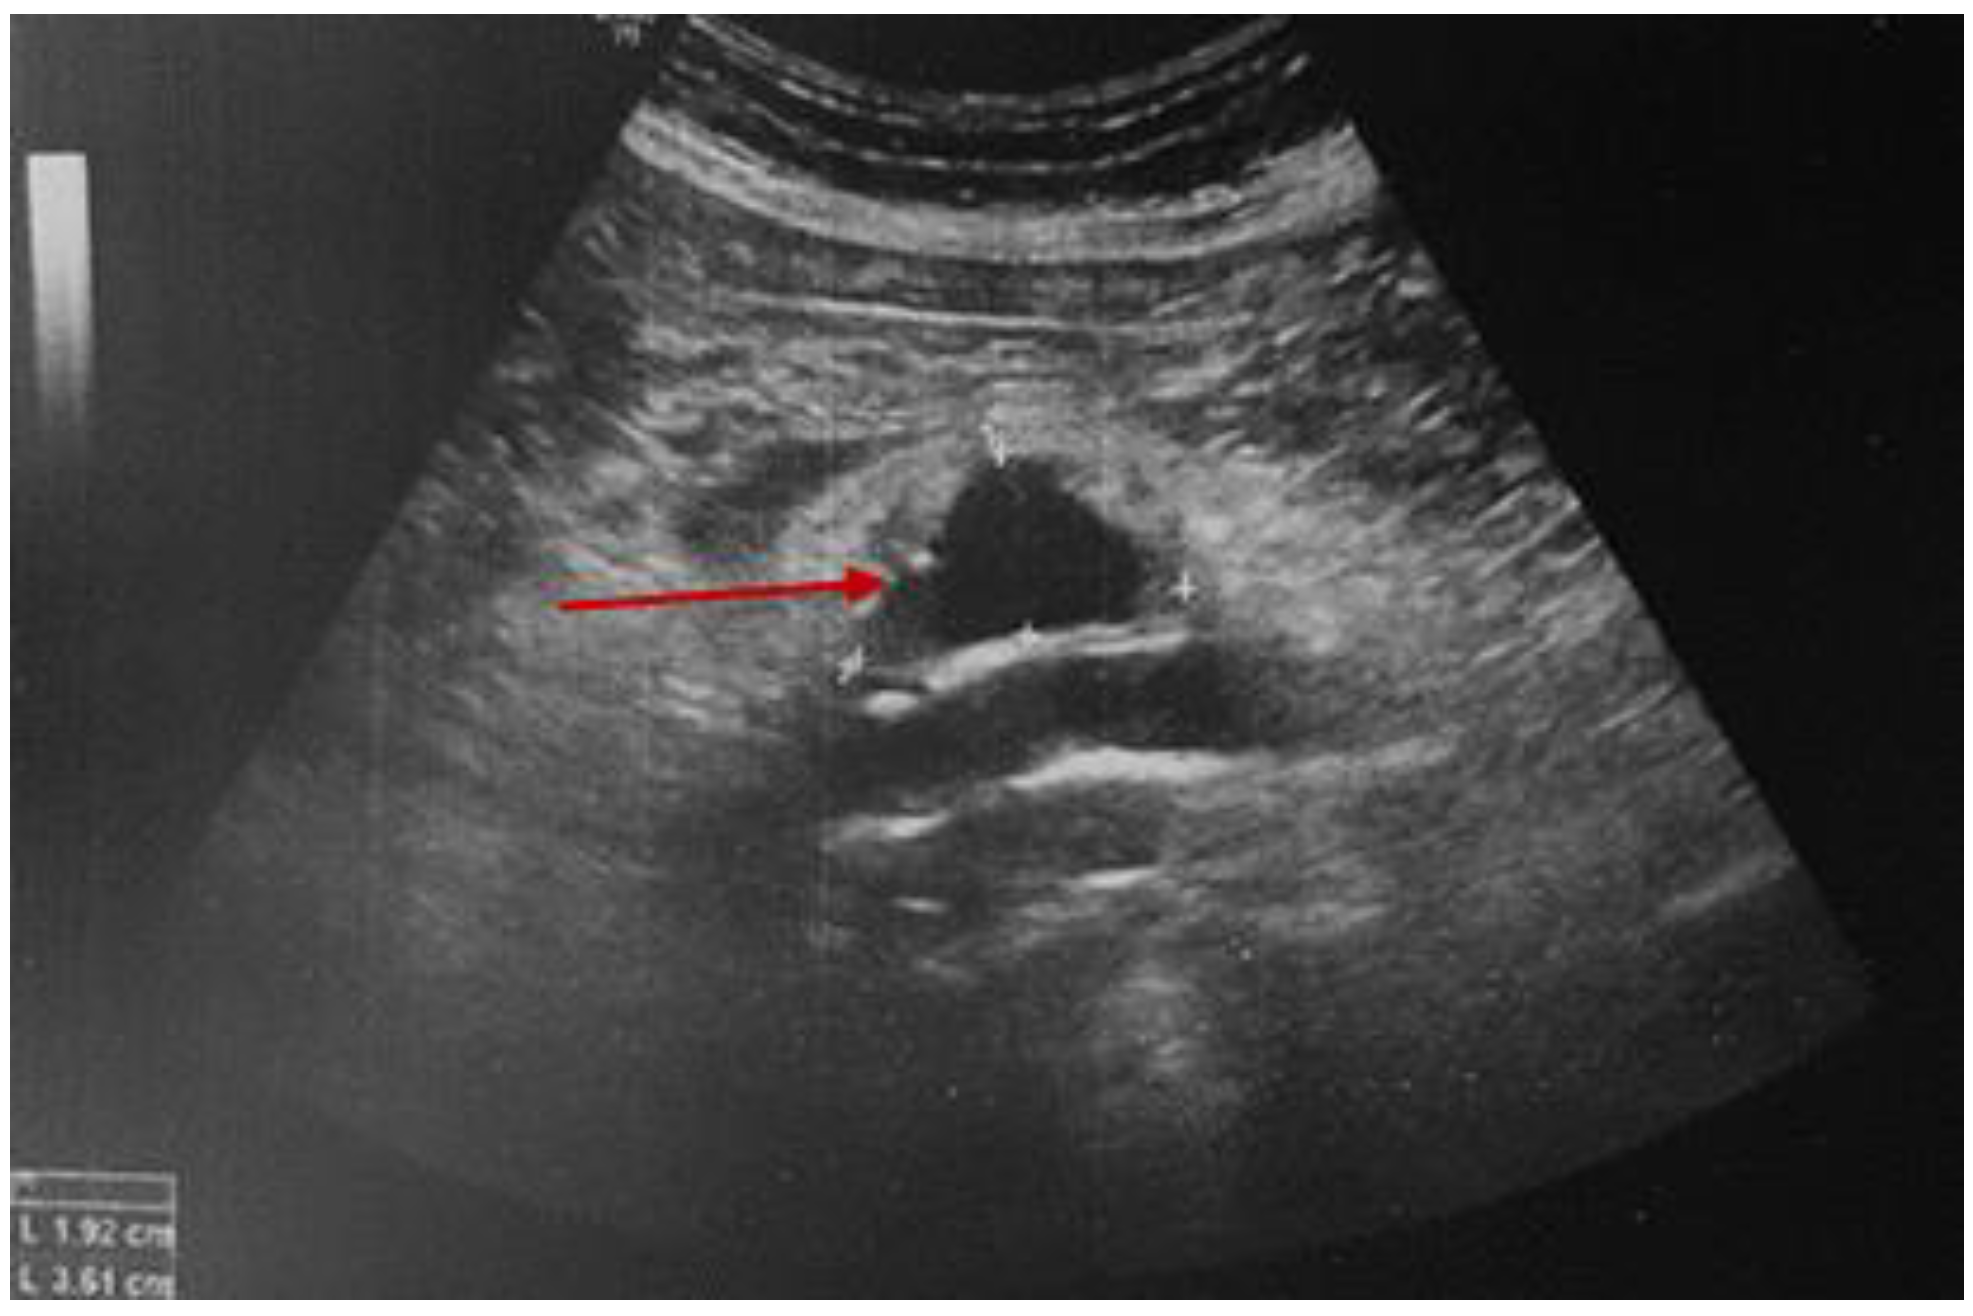

3.2.1. A Fine Index of Clinical Suspicion: Low Back Pain

3.2.2. Additional Imaging Assessments